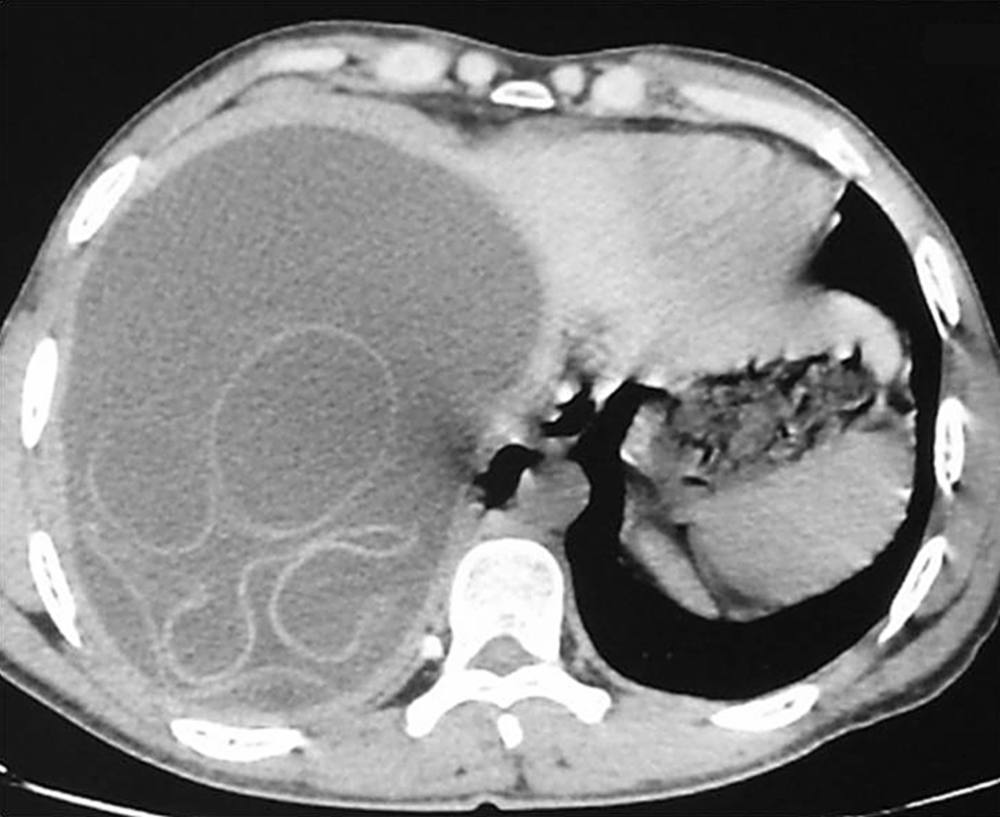

The physical examination revealed hepatomegaly with a palpable hepatic mass. Laboratory tests showed a normal white-cell count and a normal absolute eosinophil count. Ultrasonography and computed tomography of the abdomen revealed a large cyst in the right lobe of the liver.

What is the diagnosis?